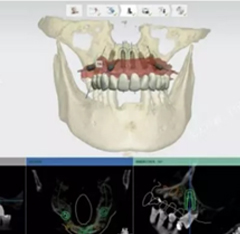

数字化种植是利用计算机图形图像技术,根据口内CT扫描数据以及光学扫描数据在计算机上重建患者颌骨立体模型,医生以此为基础,确定患者种植体嵌入位置、数量、种植深度、角度等,生成科学、精准的导板设计方案,将种植设计准确地转化到手术操作中,最后配上数字化种牙手术专用的手术工具、结合患者自身的情况制作修复体,完成种植治疗。

- 口内模拟种植,避开神经血管,设计种植方案;通过CAD/CAM激光扫描和CBCT检测等, 在计算机上重建患者口腔三维立体模型,凭借由打印技术制作的种植导板对手术全程的精准把控,减少手术时间及手术创伤,实现对缺牙的修复。

在导板辅助下可避免医生经验误差,掌控种植角度和深度,减少创伤,有效避开神经、血管等危险部位。